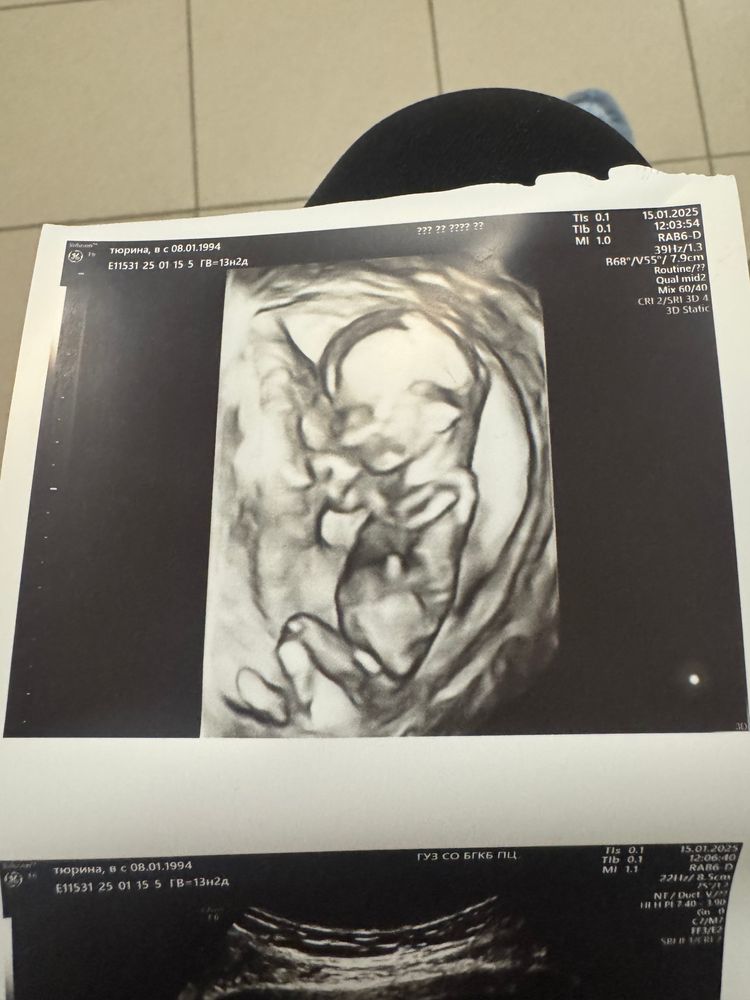

Девочка или мальчик ?

Tatiana, а вот так Изображение?

Валентина олина, я бы сказала, что на мальчика больше похоже, но по изображению полового бугорка сложно судить на таком сроке. В 2Д смотрят его наклон, а в 3Д примерно одинаково выглядит. Но я за мальчика 😊

Валентина олина, рядом с ножкой. Кажется, что бугорок, а не нога. Изображение